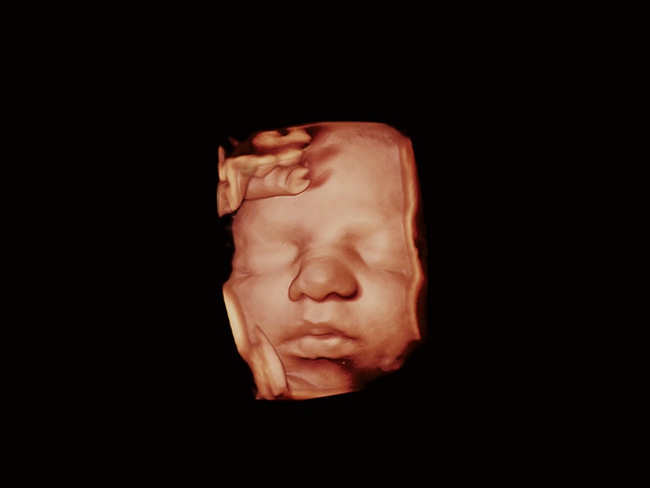

Aplio a550 может работать с линейным матричным датчиком и поддерживает новейшие монокристаллические датчики. Также Aplio a550 поддерживает большое количество дополнительных опций, таких как - SMI, Компрессионная эластография, Эластография сдвижной волны, Smart Fusion, исследования с использованием контраста (CEUS), 3D реконструкции в реальном времени (4D), функции автоматической оценки подвижности миокарда и фракции выброса.

4D: